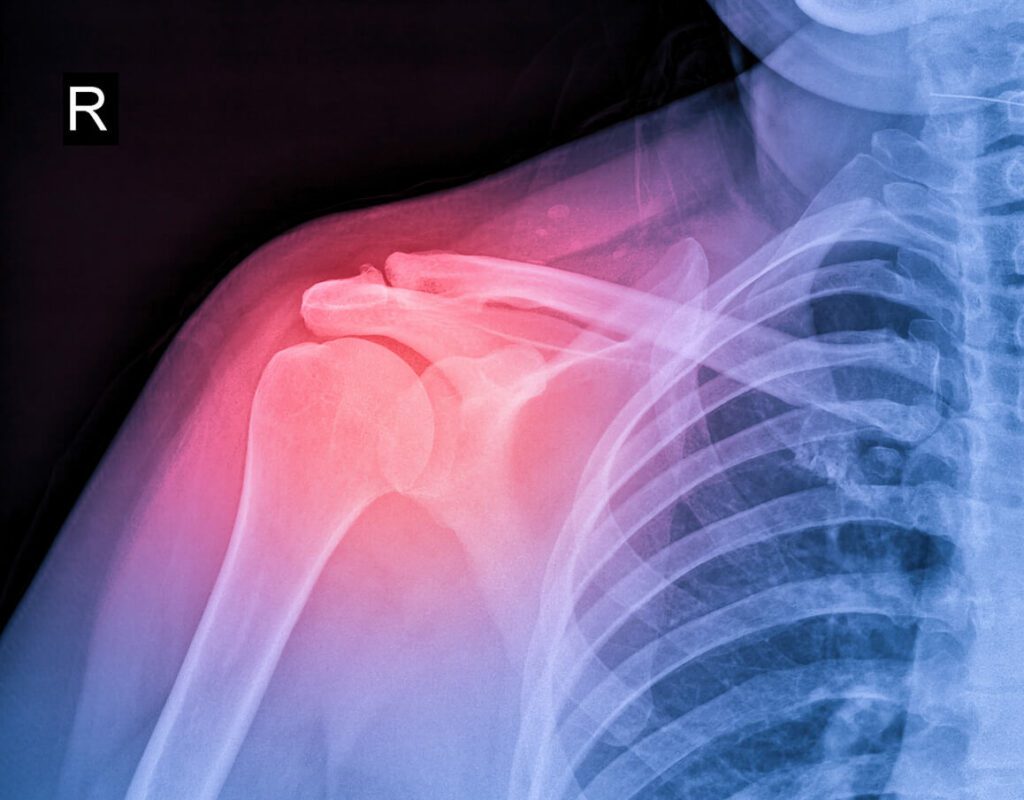

The rotator cuff is a group of muscles and tendons that stabilize your shoulder and help you lift and rotate your arm. It is one of the most important yet vulnerable parts of your body, particularly for those who perform repetitive shoulder movements.

Your shoulder is one of the most complex joints in your body – its incredible range of motion is made possible by the rotator cuff, which consists of four muscles and their tendons. Together, they stabilize the upper arm bone (humerus) in the shoulder socket and allow fluid movement.